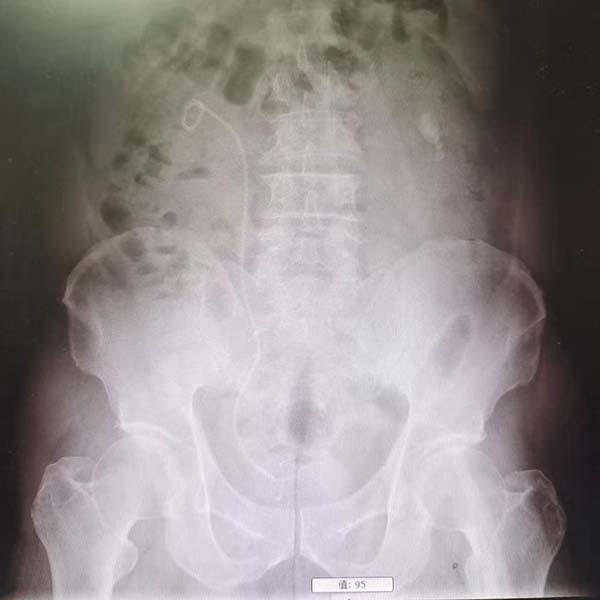

据悉,该患者因腰部剧烈疼痛并伴有血尿症状来院就诊。经检查,发现其输尿管上段嵌顿着2颗较大结石,下段1块结石。若采用传统单一的手术方式,往往需要分次进行,一次经尿道输尿管硬镜激光碎石术,一次经皮肾镜激光碎石术,不仅增加患者痛苦和经济负担,也延长了治疗周期。

手术当日,在于春虎主任的精准操作下,团队首先利用输尿管硬镜经尿道进入,顺利处理了位于输尿管下段的结石。随后,在硬镜建立的通道基础上,将纤细灵活的输尿管软镜送达位置更深、角度更刁钻的输尿管上段。软镜前端可弯曲的特性,使得医生能够无死角地观察结石情况,并利用先进的激光碎石设备将结石精准粉末化。最终,手术团队成功将输尿管上段和下段两处的结石一次性彻底清除。整个手术过程流畅,最大限度地减少了对患者正常组织的损伤。目前,该患者恢复良好,对手术效果非常满意,已经康复出院。